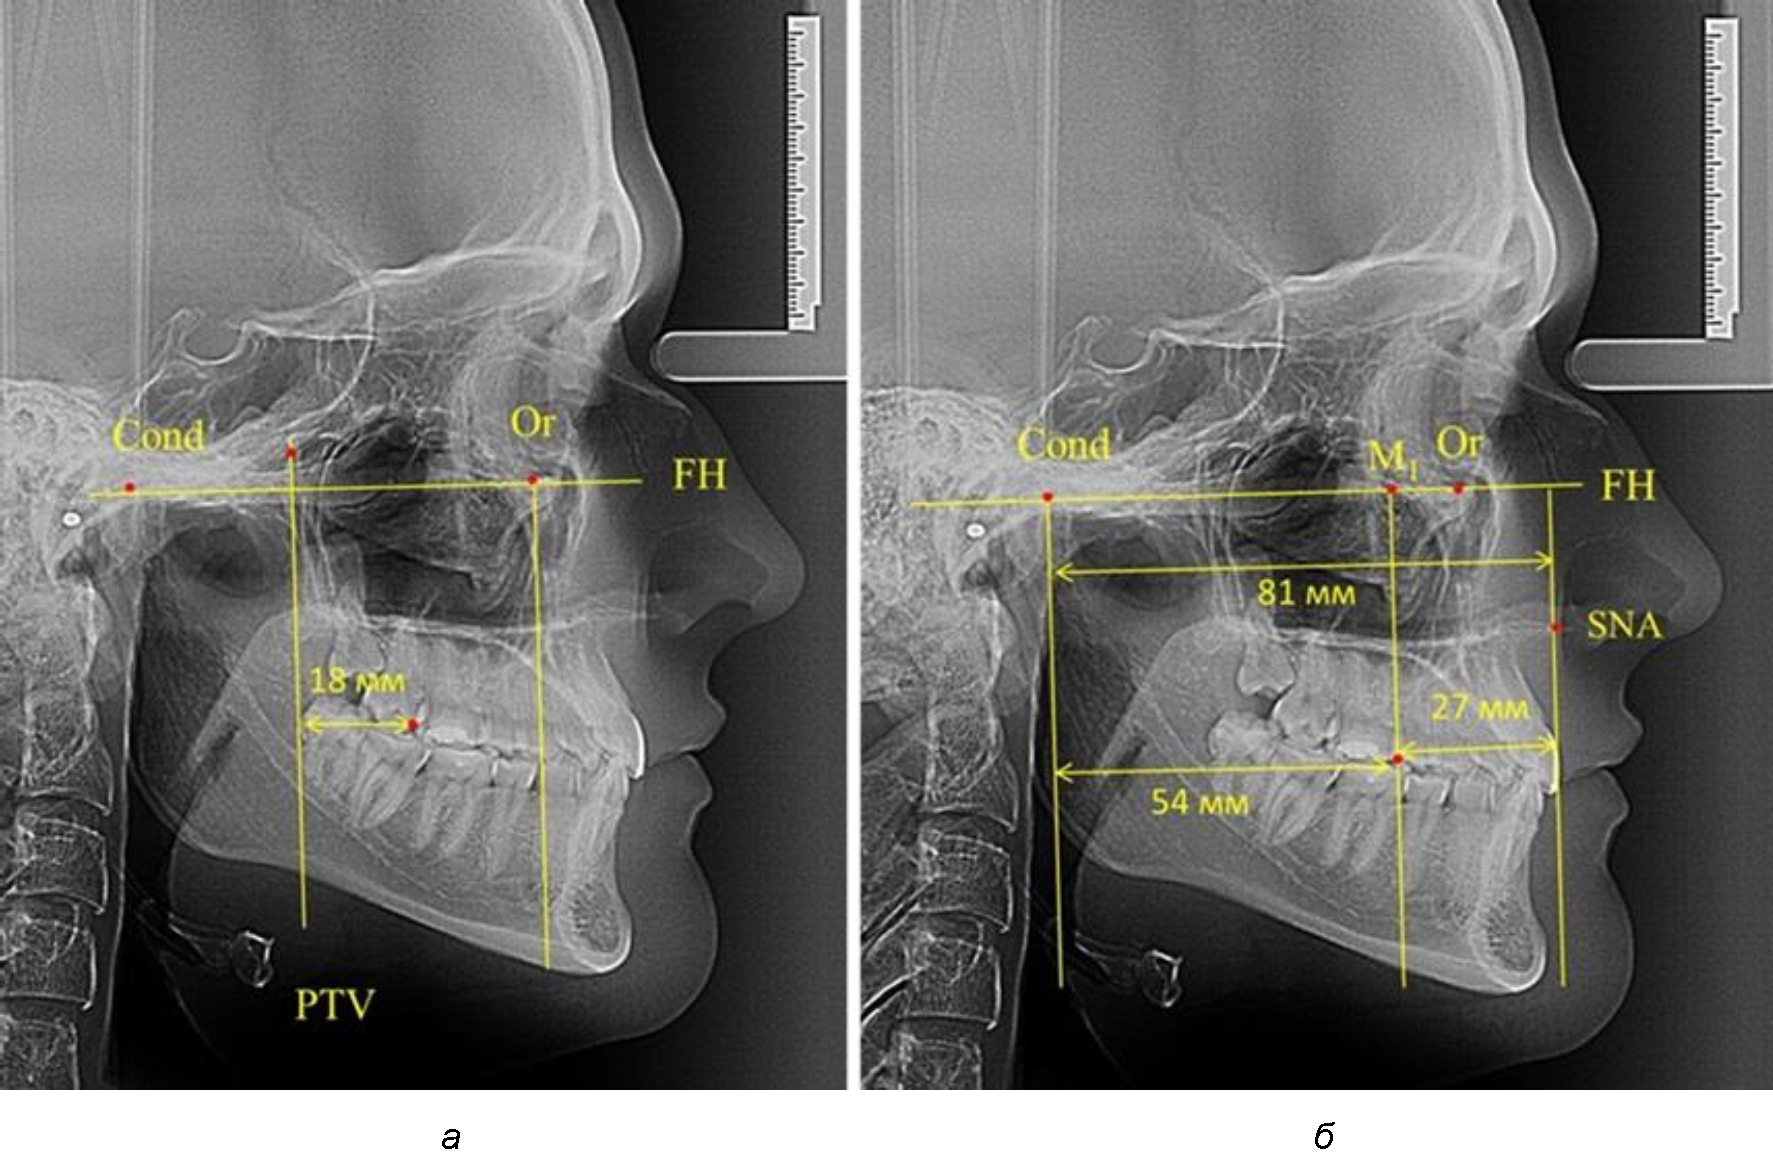

При проведении анализа к Франкфуртской горизонтали проводили передний и задний перпендикуляры. Передний спинальный перпендикуляр проходил через выступающую точку передней носовой ости (spina nasalis anterior – SNA), а задний суставной перпендикуляр опускали из кондилярной точки Cond. Молярный перпендикуляр проводили через медиальную поверхность первого постоянного моляра. Указанная вертикаль отделяла замещающие зубы постоянного прикуса от добавочных зубов (постоянных моляров), что вполне логично для анализа положения первых постоянных моляров в гнатическом комплексе (рис. 1).

Рис. 1. Метод определения положения первых верхних моляров по Ralph E. McDonald (а) и по предложенному методу (б)

Анализ проведенного исследования рентгенограмм показал существенную вариабельность практически всех линейных показателей. У молодых людей с физиологическим прикусом постоянных зубов расстояние от крыловидной вертикальной плоскости PTV до дистальной поверхности верхнего первого постоянного моляра в целом по группе составляло (18,37 ± 3,62) мм. Обращает на себя внимание большая ошибка репрезентативности из-за разницы между максимальными и минимальными значениями.

Среди анализируемых рентгенограмм минимальное значение расстояния по методу R. E. McDonald было 12 мм, а максимальное достигало 25 мм, что, по нашему мнению, обусловлено вариабельностью сагиттального размера гнатического отдела лица.

Таким образом, для прогнозирования оптимального положения первых постоянных моляров наиболее целесообразным методом явилось использование относительного показателя, что подтверждено при анализе рентгенограмм с минимальными и максимальными значениями по методу R. E. McDonald.

Так, при расстоянии от крыловидной вертикальной плоскости PTV до дистальной поверхности верхнего первого постоянного моляра в 13 мм сагиттальный размер гнатического отдела был 82 мм. При этом отношение кондилярно-спинального расстояния к кондилярно-молярному размеру (54,5) было близким к коэффициенту 1,5, что представлено на рис. 2.

В то же время при увеличенном расстоянии от крыловидной вертикальной плоскости PTV до дистальной поверхности верхнего первого постоянного моляра, равное 23 мм, сагиттальный размер гнатического отдела составил 92 мм. При этом отношение кондилярно-спинального расстояния к кондилярно-молярному размеру (30,5), так же, как и при малых размерах, было близким к коэффициенту 1,5, что представлено на рис. 3.